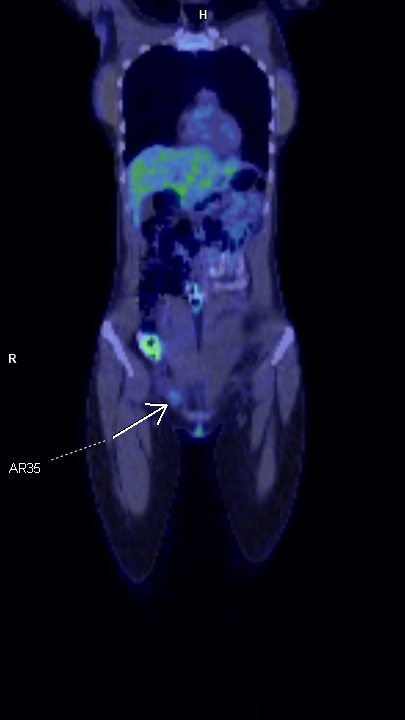

Figura 3: coronal PET-CT la diagnostic iniţial

Endometrioza este o patologie benignă dar cu rată de recurentă mare; cazul prezentat este al unei paciente cu o leziune expansivă de perete abdominal inferior în vecinătatea regiunii inghinale drepte pentru care a efectuat examinare PET CT pentru diagnostic și stadializare datorită suspiciunii de adenopatie de la un melanom malign – iar leziunea nu a avut captare foarte mare. După excizie și examen histopatologic diagnosticul a fost de focar de endometrioza iar examinarea postoperatorie prin rezonanță magnetică nu a evidențiat un rest sau o recidivă locală. Câțiva ani mai târziu se remarcă creșterea volumului local și examinarea prin rezonanță magnetică evidențiază un aspect tipic de endometrioză.